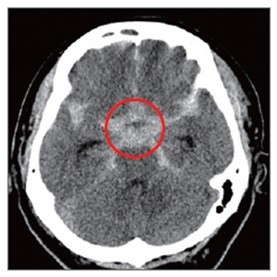

![]() |

| ▲ |

뇌동맥류를 파열 전 발견해 치료하면 95% 이상에서 좋은 결과가 나타난다. 치료는 주로 ‘클립결찰술’과 코일색전술’로 이뤄진다. 클립결찰술은 이마 부위 두개골을 열고 클립 같은 고정 핀으로 부풀어 오른 뇌동맥류를 졸라매는 수술법이다. 코일색전술은 머리를 절개하지 않고 사타구니에 있는 대퇴동맥을 통해 뇌동맥에 가느다란 도관을 넣은 뒤 뇌동맥류 내부를 백금 등으로 만들어진 특수 코일로 채워 막는 방식이다. 뇌수술이 어렵거나 직접수술이 위험성이 큰 환자에게 적합하다.